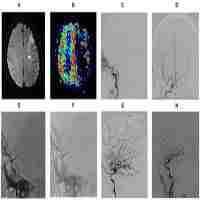

| Abstract | Symptomatic intracranial atherosclerotic disease (sICAD) remains a challenging disorder in the neurovascular field. Despite best medical treatment (BMT), the recurrence rate for stroke remains high in patients with intracranial high-grade stenosis (>70-99%). Furthermore, two large randomized trials (SAMMPRIS and VISSIT) failed to prove the efficacy of percutaneous transluminal angioplasty and stenting (PTAS) in patients with sICAD. Drug-coated balloon percutaneous transluminal angioplasty (DCB-PTA) represents an alternative treatment modality with therapeutic benefits for interventional cardiology. However, there are very few articles in the existing literature that relate to the use of DCB-PTA in sICAD patients. Here, we aimed to review the rationale underlying the use of DCB-PTA in sICAD patients and summarize recent developments in the neurovascular field. |